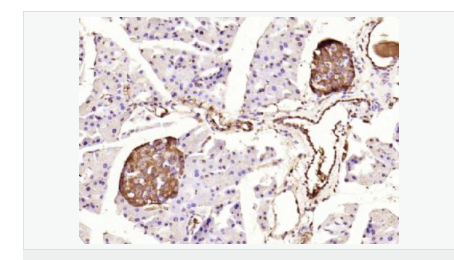

image.png